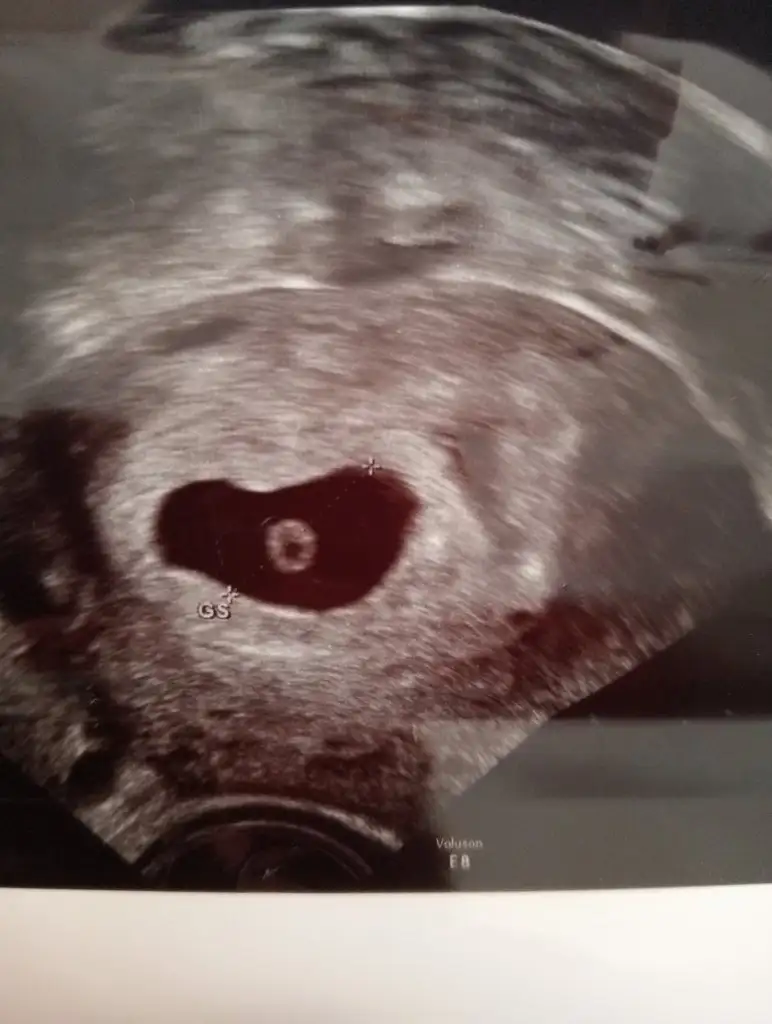

Canımm kızlar günaydın ❤️ bugün benim doğum günüm 🥳 ve ben dün hediyemi gördüm 😍 doktordan vajinal ultrason istedim ve sürpriz yumurtam oradaydı kalp atışı biraz yavaş dedi doktor 1 hafta sonra tekrar gidicem. 5+6 haftalık biraz yavaş olması normal sanki çok küçük daha 😍içim rahat 39 yaşıma girerken Rabbim bu mucizeyi nasip ettiyse vardır bir hikmeti. Hepinizi çok seviyorum ❤️

Ayyy canım yaa çok güzel bir hediye gerçekten inşallah Rabbim sağ salim kucağına almayı da nasip eder. Baya erken duymuşsun kalp atışını normal şimdilik yavaş olması. Haftaya gittiğinde gümbür gümbür duyarsın inşallah. Bize de dua etmeyi unutma emi 🥹♥️